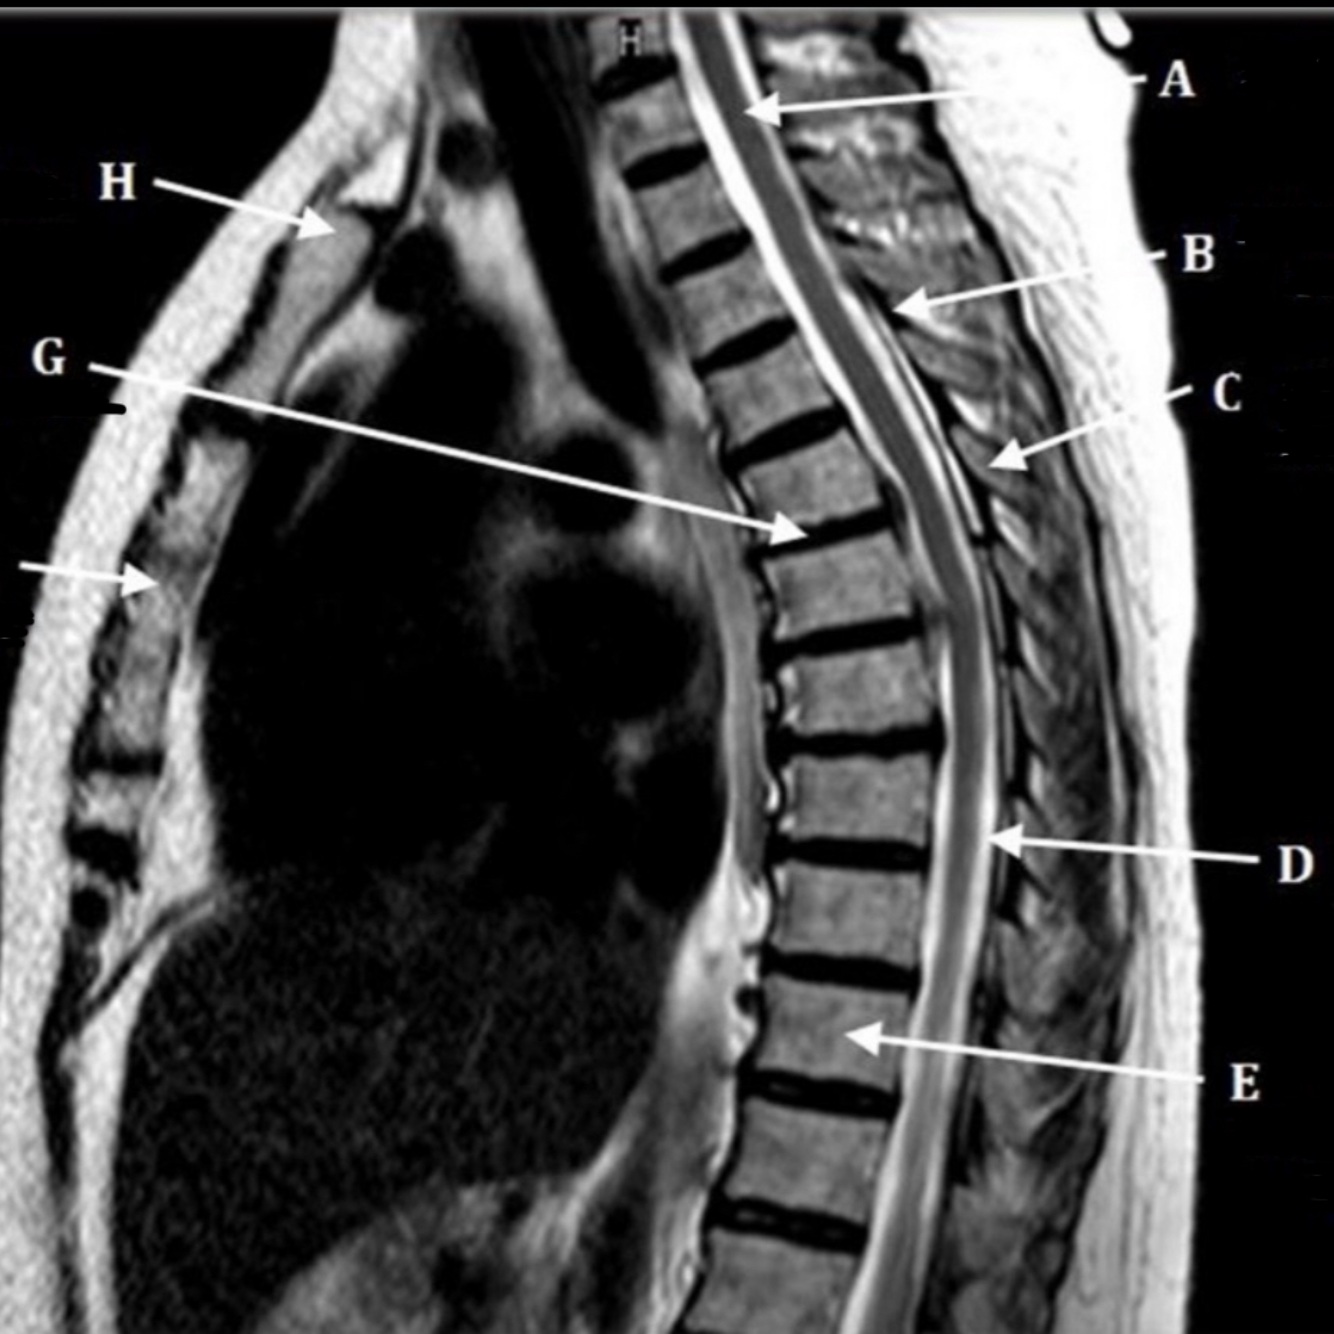

27

What is letter A?

DESCENDING THORACIC AORTA

28

What is letter B?

SPINAL CORD

29

What is letter C?

SPINOUS PROCESS

30

What is letter D?

LAMINA

31

What is letter E?

CSF

32

What is letter F?

AZYGOS VEIN

33

L4-5 HNP

34

S1 VERTEBRAL BODY

35

L5 VERTEBRAL BODY

36

L2-3 DISK SPACE

55

CEREBELLUM

56

57

58

59

60

INTERVERTEBRAL DISK SPACE

61

What is letter G?

12TH THORACIC VERTEBRAE

62

What is letter H?

7TH THORACIC VERTEBRAE

63

What is letter J?

SUPRASTERNAL NOTCH

64

What is letter K?

3RD CERVICAL VERTEBRAE

65

What is letter L?

PONS